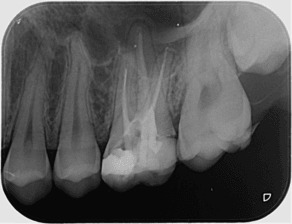

Зъбните снимки, независимо дали са секторни, панорамни зъбни снимки, телерентгенографии или друг вид се съхраняват на нашите сървъри неограничено дълго време.

Зъбните снимки са налични в няколко различни файлови формата - DICOM (DCM), PNG и JPG, което улеснява свалянето им на личните компютри.

Денталните медици могат с лекота да правят всички необходими обработки и измервания на дигиталните зъбни снимки, което улеснява подготовката за лечебния процес на пациента.